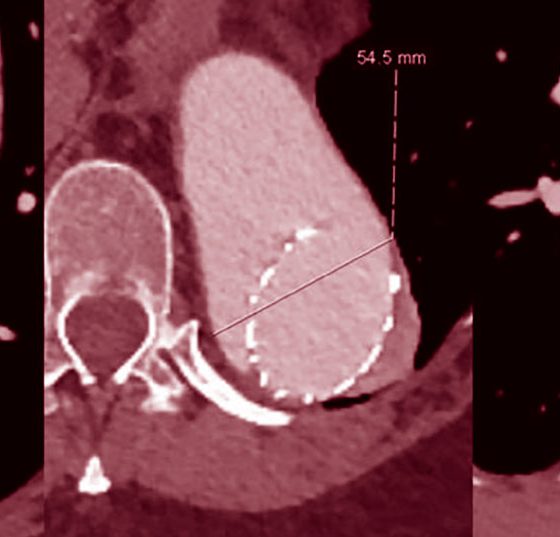

• Arterio-venöse Malformationen

Gefässmalformation im Kopf – Was nun?

Hauptmanifestation einer symptomatischen arterio-venösen Malformation (AVM) ist eine intrakranielle Blutung, typischerweise subarachnoidal oder intrazerebral als Folge der Ruptur bei lokalisiert destruktivem Gefässwandumbau. Weitere typische Symptome bestehen entweder als Reiz­erscheinung und...…